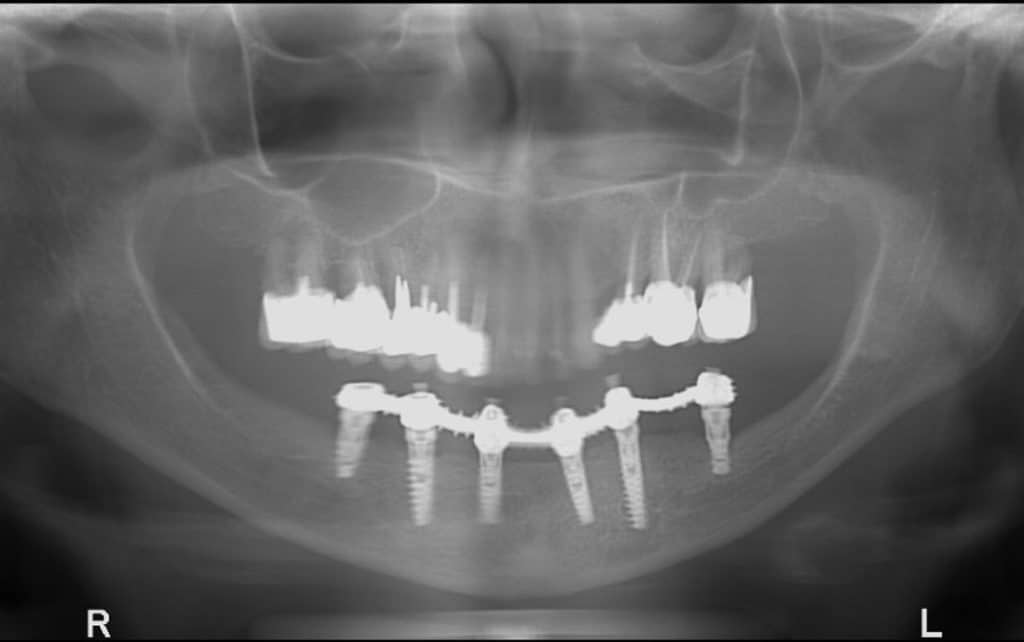

השתלת שיניים שנכשלה לסת תחתונה

במהלך השתלת השיניים הסטנדרטית רופא השיניים מעגן אל עצמות הלסת שלנו שתלים דנטליים. אלו למעשה הברגות מתכתיות אל תוך עצם הלסת, שעליהן יושב גשר דנטלי המחזיק את מערכת הכתרים, המחליפה את מערכת השיניים שלנו.

לאחר שעוגנו, השתלים הדנטליים עוברים מעצם הלסת דרך החניכיים והחוצה אל הגשר היושב בחלל הפה.

חשוב לדעת שזיהוי של הכישלון חייב להתבצע על ידי רופא השיניים המטפל ולכן, כדאי לגשת למרפאה אם אחד או יותר מהסימנים מופיעים ולעבור אבחון מדוקדק שכולל צילום פנורמי וסריקה של חלל הפה.

השלב השני הוא שלב של האבחון – רופא השיניים חייב לאבחן את הגורמים לכישלון על מנת להימנע מכישלון נוסף בהמשך. הוא עושה זאת ע"י הדמית CT עדכנית שמלווה כמובן בבדיקה פיזית שלו בחלל הפה.